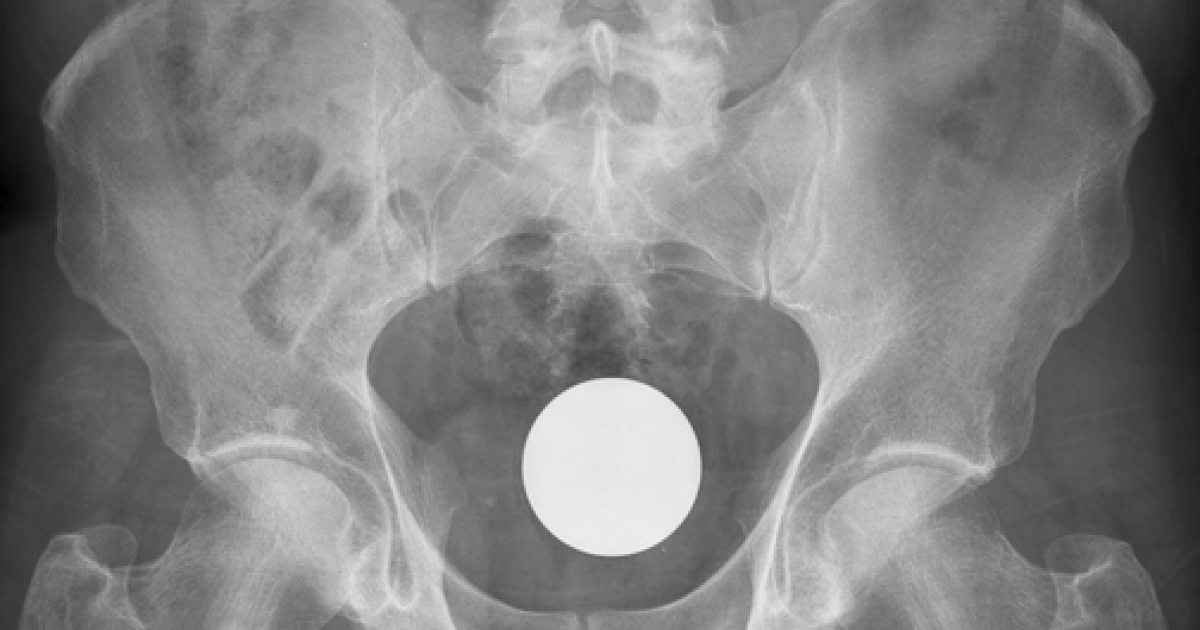

NASCONDEVANO 167 OVULI DI HASHISH NELL'INTESTINO: TRE ARRESTI. Tre giovani teramani, di età tra i 20 ed i 27 anni, sono finiti in manette ieri pomeriggio con l'accusa di traffico internazionale di sostanze stupefacenti. Il blitz anti-droga è scatato dopo che alla Questura di Teramo era giunta una "soffiata" circa il possibile arrivo in città di una partita i droga. Così sono partite le indagini che si sono concentrate da subito sui tre. Quando però una pattuglia della Questura è andata a bussare alla porta dell'abitazione i tre si sono subito innervositi ma in casa non c'era nulla. Gli agenti erano sicuri della notizia di reato così si è deciso di portarli al "Mazzini" di Teramo per vedere se, per caso, avessero ingerito lo stupefacente allo scopo di evitare l'arresto. E così è stato. La radiografia dell'ospedale ha da subito evidenziato la presenza di ovuli nell'intestino dei ragazzi. Sottoposti a specifico trattamento medico, in due giorni, hanno espulslo ben 167 ovuli di droga per un totale di 1 Kg e 240 grammi di hashish. Secondo i medici del nosocomio teramano hanno rischiato anche la morte perchè i contenitori, benchè termosaldati, potevano aprirsi ed intossicare gli intestini dei giovani fino a procurare uno stato di coma. Adesso le indagini sono indirizzate a scoprire il fornitore dello stupefacente che, da quanto si è saputo, è straniero. Il gruppetto, infatti, veniva da un viaggio all'estero e la droga era stata ingoiata proprio per evitare la polizia di frontiera.